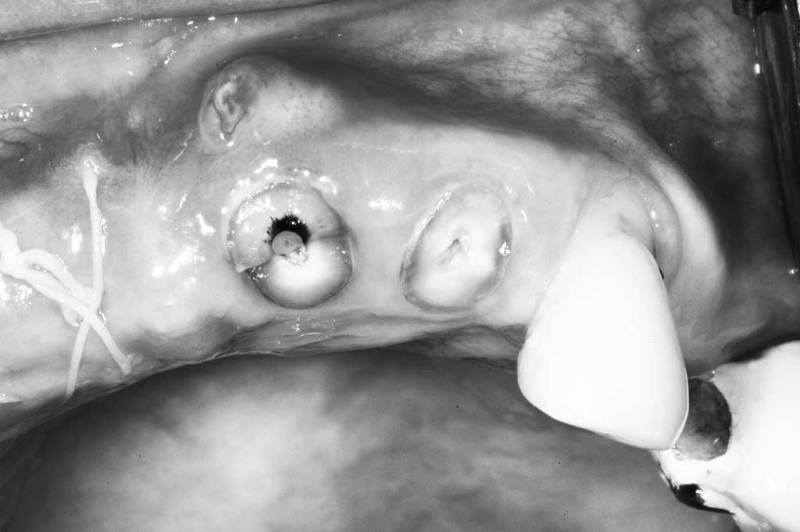

窩洞保存術術中